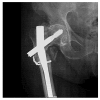

Failure of osteosynthesis implants is an intricate matter with challenging management that calls for efficient investigation and prevention. Using implant retrieval analysis combined with standard radiological examination, we evaluated the main causes for osteosynthesis implant breakdown and the relations among them for a series of cases. Twenty-one patients diagnosed with implant failure were assessed for this work. For metallurgical analysis, microscopy techniques such as scanning electron microscopy (SEM), stereomicroscopy, and optical microscopy were employed. The results showed that material structural deficiencies (nine patients) and faulty surgical techniques (eight patients) were the main causes for failure. An important number of patients presented with material structural deficiencies superimposed on an imperfect osteosynthesis technique (six patients). Consequently, the importance of failure retrieval analysis should not be overlooked, and in combination with other investigational techniques, must provide information for both implant manufacturing and design improvement, as well as osteosynthesis technique optimization.